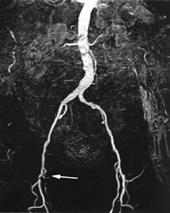

MR angiografija perifernih krvnih sudova koristi se još od 1992. godine u evaluaciji okluzivne bolesti (Slika 6.), uz prateće promene protokola tehnika (2-D TOF, 3-D TOF bez kontrasta, a u novije vreme sa kontrastom), zavojnica (za telo, za ekstremitete) i usavršavanje aparata (automatski pokretni sto). Time je postignuto skraćenje vremena pregleda, bolja preciznosti određivanja stepena stenoze krvnog suda sa što manje artefakata i prikazivanje velikog segmenta vaskularnog sistema, od aorte do stopala. S toga se i senzitivnost i specifičnost ove metode kretala od 88% do 100% u brojnim objavljenim studijama. Danas MRA sa kontrastom predstavlja metod izbor u evaluaciji vaskularnih bolesti perifernih arterija i trbalo bi je indikovati nakon inicijalne Doppler sonografije.

Slika 6. MR angiografija: stenoza desne femoralne arterije.